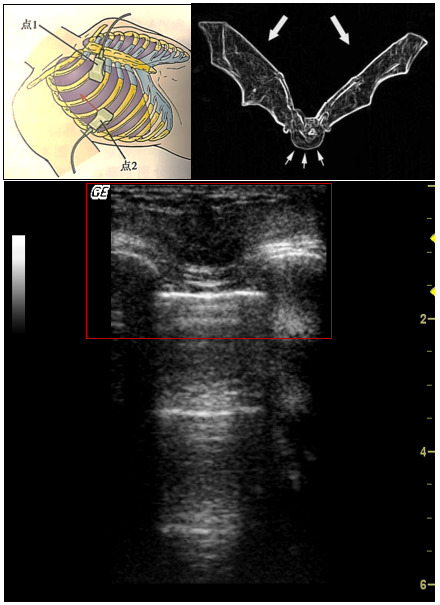

正常肺的超声表现

进行肺部超声检查时,首先要确定胸膜的位置,将探头置于两个肋骨之间时,会看到屏幕外围两侧有宽约2 cm的高回声曲线,胸膜线位于屏幕中央,两侧肋骨下方,在脏层胸膜和壁层胸膜交界处形成的第一条高回声曲线,其形态类似蝙蝠,故称为“蝙蝠征”。之后再去观察有无“肺滑动征”,即脏层胸膜和壁层胸膜随呼吸而相互滑动或闪动,肺滑动征提升我们两层胸膜之间无气无水,胸膜无黏连或融合。此外,在超声上还能看到A线,即在胸膜线下与胸膜线平行、相互之间等距的高回声曲线。正常肺充气状态即为A线+肺滑动征。

图片

M型模式下的胸壁和胸膜滑动如下图所示,胸壁相对不动,呈横纹表现,肺滑动引起沙粒样改变,称为海岸征或沙滩征。近场显示胸壁层的静态表现(海),远场显示动态胸膜滑动的运动征象(海岸)。

注:左图为B型超声,右图为M型超声